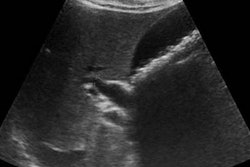

The FAST exam is used to evaluate injured patients with the goal of identifying hemoperitoneum associated with intra-abdominal injuries. Most research assessing the utility of FAST has involved adult patients, with randomized clinical trials finding that an initial FAST exam yielded lower utilization of abdominal CT, a shorter hospital length of stay, fewer complications, and fewer hospital charges.

All FAST exams were performed using a Zonare Z.One Ultra portable ultrasound scanner (Mindray Medical International) with 3.5-MHz and 5.0-MHz transducers. Patients received the standard FAST exam, including views of Morison's pouch, the splenorenal fossa, long and short axes of the pelvis, and subxiphoid.